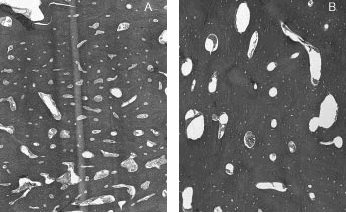

En la tomografía axial computarizada (TAC) de rodilla derecha (fig. 3 A) se observan calcificaciones periarticulares. En la TAC de la porción superior de la pierna derecha (fig. 3 B) destacan gruesas calcificaciones en la porción anterior de la tibia, de bordes lobulados.

Figura 3. Tomografía axial computarizada de rodilla derecha (A) y porción superior de la pierna derecha (B).